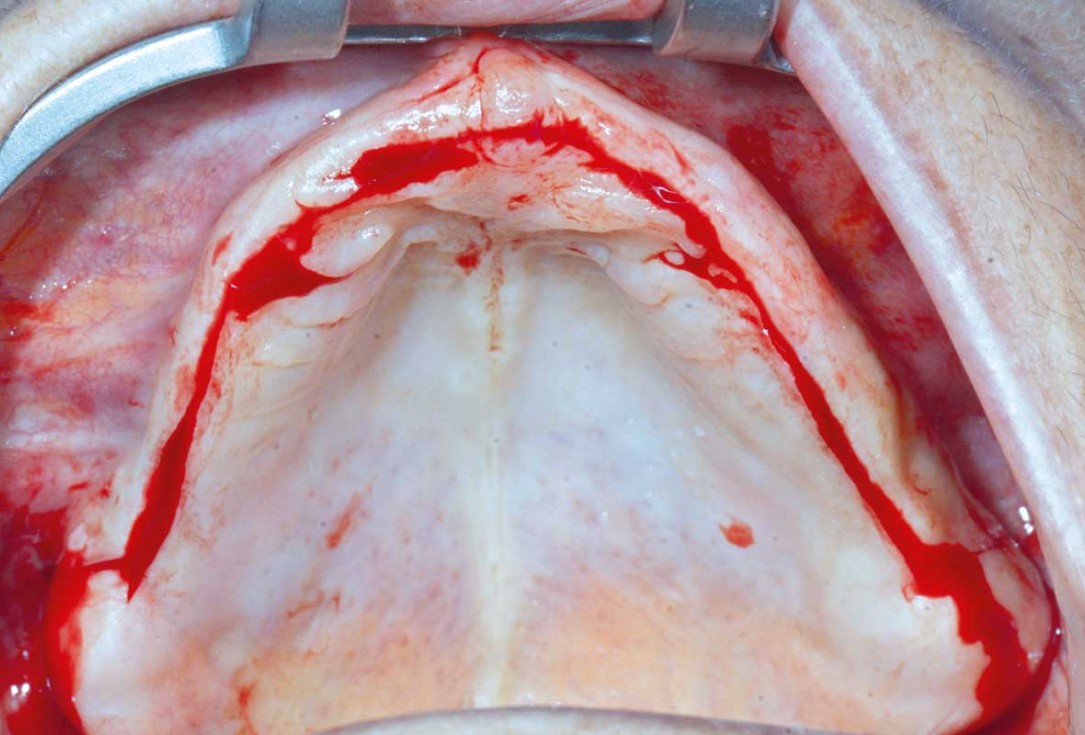

Full arch GBR using cerabone®, maxgraft® and Jason® membrane with simultaneous implantation of 6 Straumann® implants - Dres. A. Signorio and G. Molina